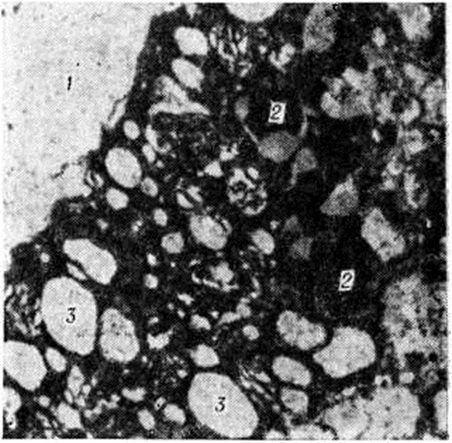

Геморрагический инсульт, как правило, возникает при заболеваниях, протекающих с повышенным артериальное давление. Это обусловлено тем, что сосудистые кризы (смотри полный свод знаний), характерные для гипертонической болезни (смотри полный свод знаний) и артериальной гипертензии (смотри полный свод знаний Гипертензия артериальная), приводят к морфологический изменениям стенок внутримозговых сосудов с нарушением их проницаемости — плазматическому пропитыванию (рисунок 1), некрозам (рисунок 2), образованию микроаневризм (рисунок 3) и их разрывам. Разрыв врождённых артериальных и артериовенозных аневризм может протекать на фоне нормального давления. Преимущественная локализация и характер геморрагий определяются особенностями ангиоархитектоники различных отделов мозга. При гипертонической болезни наиболее тяжёлым изменениям подвергаются сосуды подкорковых узлов и зрительного бугра. Это объясняется отхождением глубоких ветвей под прямым углом от средней мозговой артерии, являющейся продолжением внутренней сонной артерии, и незначительным числом анастомозов сосудов в этой области. В связи с этим на вскрытии кровоизлияния наиболее часто (40%) обнаруживаются в подкорковых узлах с распространением в прилежащее белое вещество (так называемый латеральные кровоизлияния, то есть расположенные латерально от внутренней капсулы, рисунок 4). Второе место по частоте (16%) занимают обширные кровоизлияния, разрушающие подкорковые узлы, внутреннюю капсулу, зрительный бугор (так называемый смешанные кровоизлияния — рисунок 5). Кровоизлияния в зрительный бугор (так называемый медиальные — рисунок 6) составляют 10%, в мозжечок — 6—10%, в мост мозга — 5% от общего числа внутримозговых геморрагий. Кровоизлияния только в белое вещество полушарий мозга встречаются крайне редко. Подразделение полушарных кровоизлияний на латеральные, медиальные и смешанные имеет особое значение в связи с хирургическим лечением геморрагического Инсульт.

Электронно-микроскопическое исследование коры мозга человека при Инсульт выявляет различные ультраструктурные изменения нейронов, глиальных элементов и капилляров. В ультраструктуре капилляров можно выделить следующие основные патологический изменения: дистрофию стенки капилляра с накоплением в ней лизосомальных включений, липофусциновых гранул, распадом митохондрий, расслоение и вакуолизацию базальной мембраны (рисунок 18). Кроме того, отмечается разрастание и гиперплазия эндотелия. Ультраструктурные повреждения капиллярной стенки сопровождаются разнообразными изменениями из просвета. Обнаруживается ряд изменений основных субмикроскопических компонентов нейронов. Наиболее характерны нейроны, изменённые по гиперхромному типу (рисунок 19), что сочетается с пикнозом ядра, разрушением митохондрий, деструкцией гранулярного и агранулярного ретикулума, наличием большого числа вакуолей и лизосомальных включений, и нейроны с явлениями хроматолиза (рисунок 20), который сопровождается исчезновением цитоплазматических включений, растворением мембранных структур, образованием вместо цистерн ретикулума групп дискретных пузырьков, отсутствием рибосом, набуханием митохондрий, появлением вакуолей. Изменение ультраструктуры капилляров и нейронов сопровождается отёком астроцитарных отростков, скоплением тел глиальных клеток вокруг патологически изменённых элементов. В области расположения патологически изменённого капилляра наблюдаются клетки-тени (клетки в состоянии кариоцитолиза). Прослеживается зависимость изменений элементов одной цепи: нейрон — капилляр — глия.